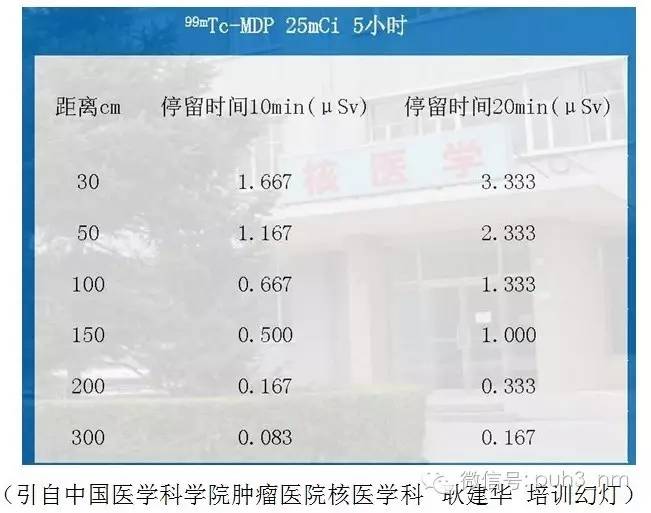

以核医学最常用的核素99mTc为例,其半衰期6小时。注入患者体内后随着时间会很快的衰减,同时加上药物从体内的代谢和排泄,一般在患者体内的有效半衰期最多为2-3个小时。以使用核素量较大的骨显像为例,常规注射量25mci,辐射剂量约为4.2mSv,明显低于常规胸部CT平扫的剂量(表1,数据来源于中华医学会核医学分会)。同时由于放射性药物具有很高的生物学探测灵敏度,与CT或MR造影剂相比,所需化学量很少,不干扰破坏体内生理过程的平衡状态,通常没有过敏反应。注射核素显像剂以后,不会干扰其他影像检查(如超声、CT、MR等)。因此,在专业核医学医师的指引下,患者可以放心接受核医学诊疗。

同样以目前用药量相对较大的全身骨显像为例。患者注射25mci骨显像剂后2-5小时进行显像,检查结束后以不同的距离、固定时间测定其对周围的辐射剂量(见下图,数据来源于中华医学会核医学分会),可以看出在距患者10cm的距离,接触患者10分钟,需要同时接触600个患者,才能达到1mSv的公众剂量剂量限值。即使护士对于患者进行近距离操作,一般也不超过10分钟。由此可见尽管我们建议受检者在检查当要日尽量避免与婴幼儿及孕妇的密切接触,但实际上当患者检查结束之后体内的放射性水平已在相当低的水平,一般不会对与之密切接触的周围人员造成影响。